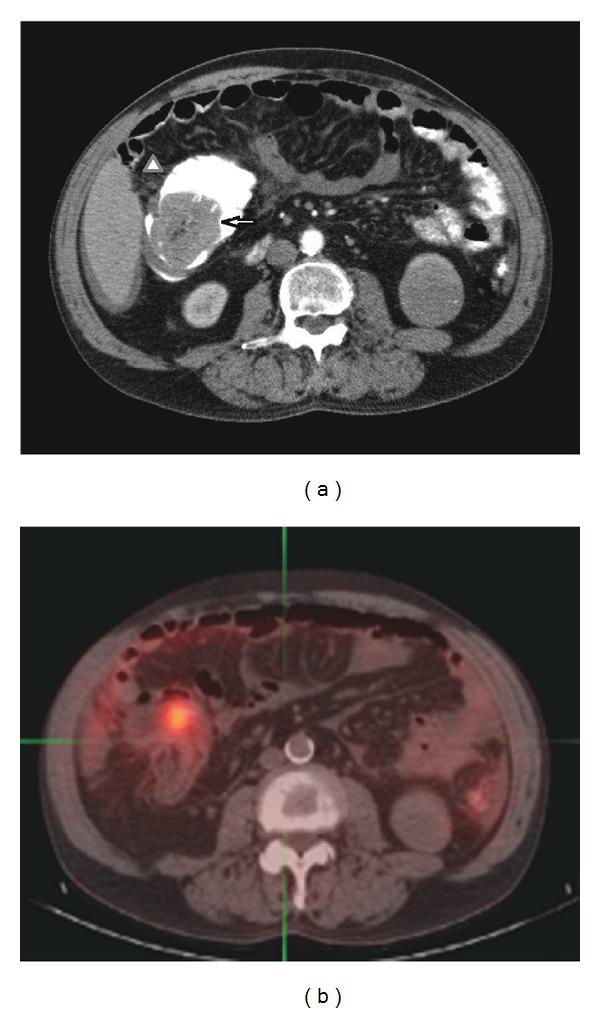

We report a case of synchronous primary colonic adenocarcinoma and malignant mesothelioma. A 61-year-old male presented with a six-month history of fatigue and weight loss. An abdominal computed tomography (CT) scan showed a 5.8 cm partially obstructing mass in the cecum with ascites and peritoneal thickening. A biopsy of the large mass showed an adenocarcinoma. Because the patient was clinically thought to be a T4 colon carcinoma with peritoneal metastatic lesions (M1), prior to initiating chemotherapy, a debulking right hemicolectomy was performed. Resection of the colon and ileum revealed a T3N0 colonic mucinous adenocarcinoma and concurrent diffuse malignant peritoneal mesothelioma. Presenting synchronous colonic and peritoneal mesothelial primary malignancies are exceedingly rare but must be considered to prevent incorrect clinical staging.

我们报告一例同时发生的原发性结肠腺癌和恶性间皮瘤病例。一名61岁男性,有6个月的疲劳和体重减轻病史。腹部计算机断层扫描(CT)显示盲肠有一个5.8厘米的部分梗阻性肿块,伴有腹水和腹膜增厚。对大肿块进行活检显示为腺癌。由于临床上认为该患者为伴有腹膜转移灶(M1)的T4期结肠癌,在开始化疗之前,进行了减瘤性右半结肠切除术。结肠和回肠切除术后显示为T3N0期结肠黏液腺癌并伴有弥漫性恶性腹膜间皮瘤。同时出现的结肠和腹膜间皮原发性恶性肿瘤极为罕见,但必须予以考虑,以防止临床分期错误。